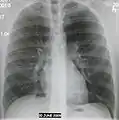

AP CXR showing pneumonia of the lingula of the left lung

Right upper lobe pneumonia as marked by the circle.

Left upper lobe pneumonia with a small pleural effusion.